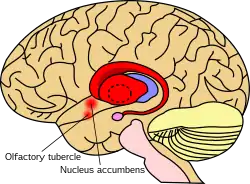

In primates, the striatum is divided into a ventral striatum, and a dorsal striatum, subdivisions that are based upon function and connections. The ventral striatum consists of the nucleus accumbens and the olfactory tubercle. The dorsal striatum consists of the caudate nucleus and the putamen. A white matter, nerve tract (the internal capsule) in the dorsal striatum separates the caudate nucleus and the putamen.[4] Anatomically, the term striatum describes its striped (striated) appearance of grey-and-white matter.[10]

The ventral striatum is composed of the nucleus accumbens and the olfactory tubercle.[4][11] The nucleus accumbens is made up of the nucleus accumbens core and the nucleus accumbens shell, which differ by neural populations. The olfactory tubercle receives input from the olfactory bulb but has not been shown to play a role in processing smell.[11] In non-primate species, the islands of Calleja are included.[12] The ventral striatum is associated with the limbic system and has been implicated as a vital part of the circuitry for decision making and reward-related behavior.[13][14]